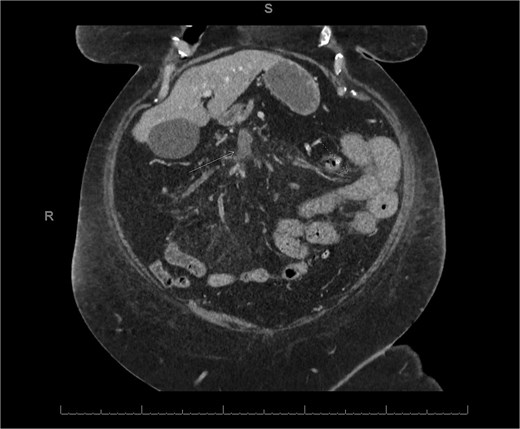

A 45-year-old male presenting with a 10-day history of isolated right lower quadrant (RLQ) abdominal pain. His history included deep vein thrombosis, coronary artery disease with prior STEMI, left anterior descending artery stenting in 2014, and ongoing antiplatelet therapy with aspirin. Upon admission, RLG tenderness was noted. Laboratory revealed leucocytosis (WBC 16 G/L) and elevated CRP (70 mg/L). E-CT revealed superior mesenteric and portal systems thrombosis with ischemia of a small bowel loop in the RLQ, characterized by absent bowel wall enhancement and free fluid (Fig. 4). Besides these findings, he was managed conservatively with a UFH bolus of 5000 U/l, followed by a continuous infusion of 36 000 U/l over 24 h (target INR 0. 35–0. 7), Ceftriaxone and Metronidazole, bowel rest, and ICU monitoring for 48 h. Clinical and biological improvement was rapid. E-CT on the second day showed no signs of perforation (Fig. 5). He was discharged after 7 days on LMWH (enoxaparin sodium 90 mg every 12 h). Twenty days later, he re-presented with acute RLQ pain and localized peritonism. E-CT revealed a covered perforation of the previously ischemic small bowel loop (Fig. 6). A segmental bowel resection with primary anastomosis was performed by laparotomy (Fig. 7). The postoperative course was uneventful, and he was discharged on postoperative day 4 with sodium enoxaparin 90 mg/12 h.

E-CT in the second patient at admission. White arrows showing porto-mesenteric thrombosis. Dashed arrows indicate a portion of small bowel loop ischemia in the right lower quadrant characterized by the absence of bowel wall enhancement and free fluid.